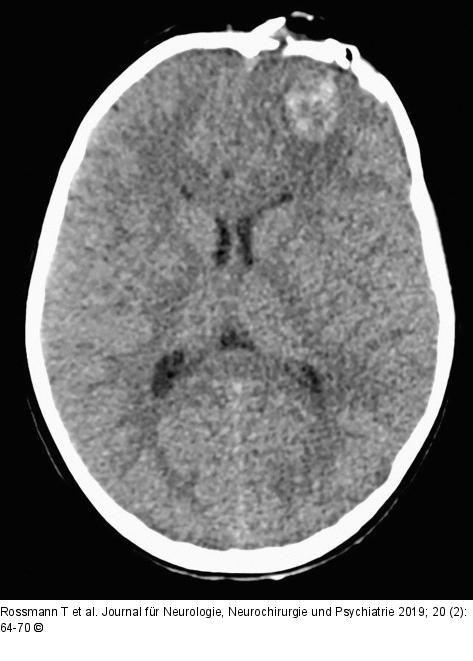

Abbildung 6: Nativ-CCT Nativ-CCT bei Aufnahme im Donauspital |